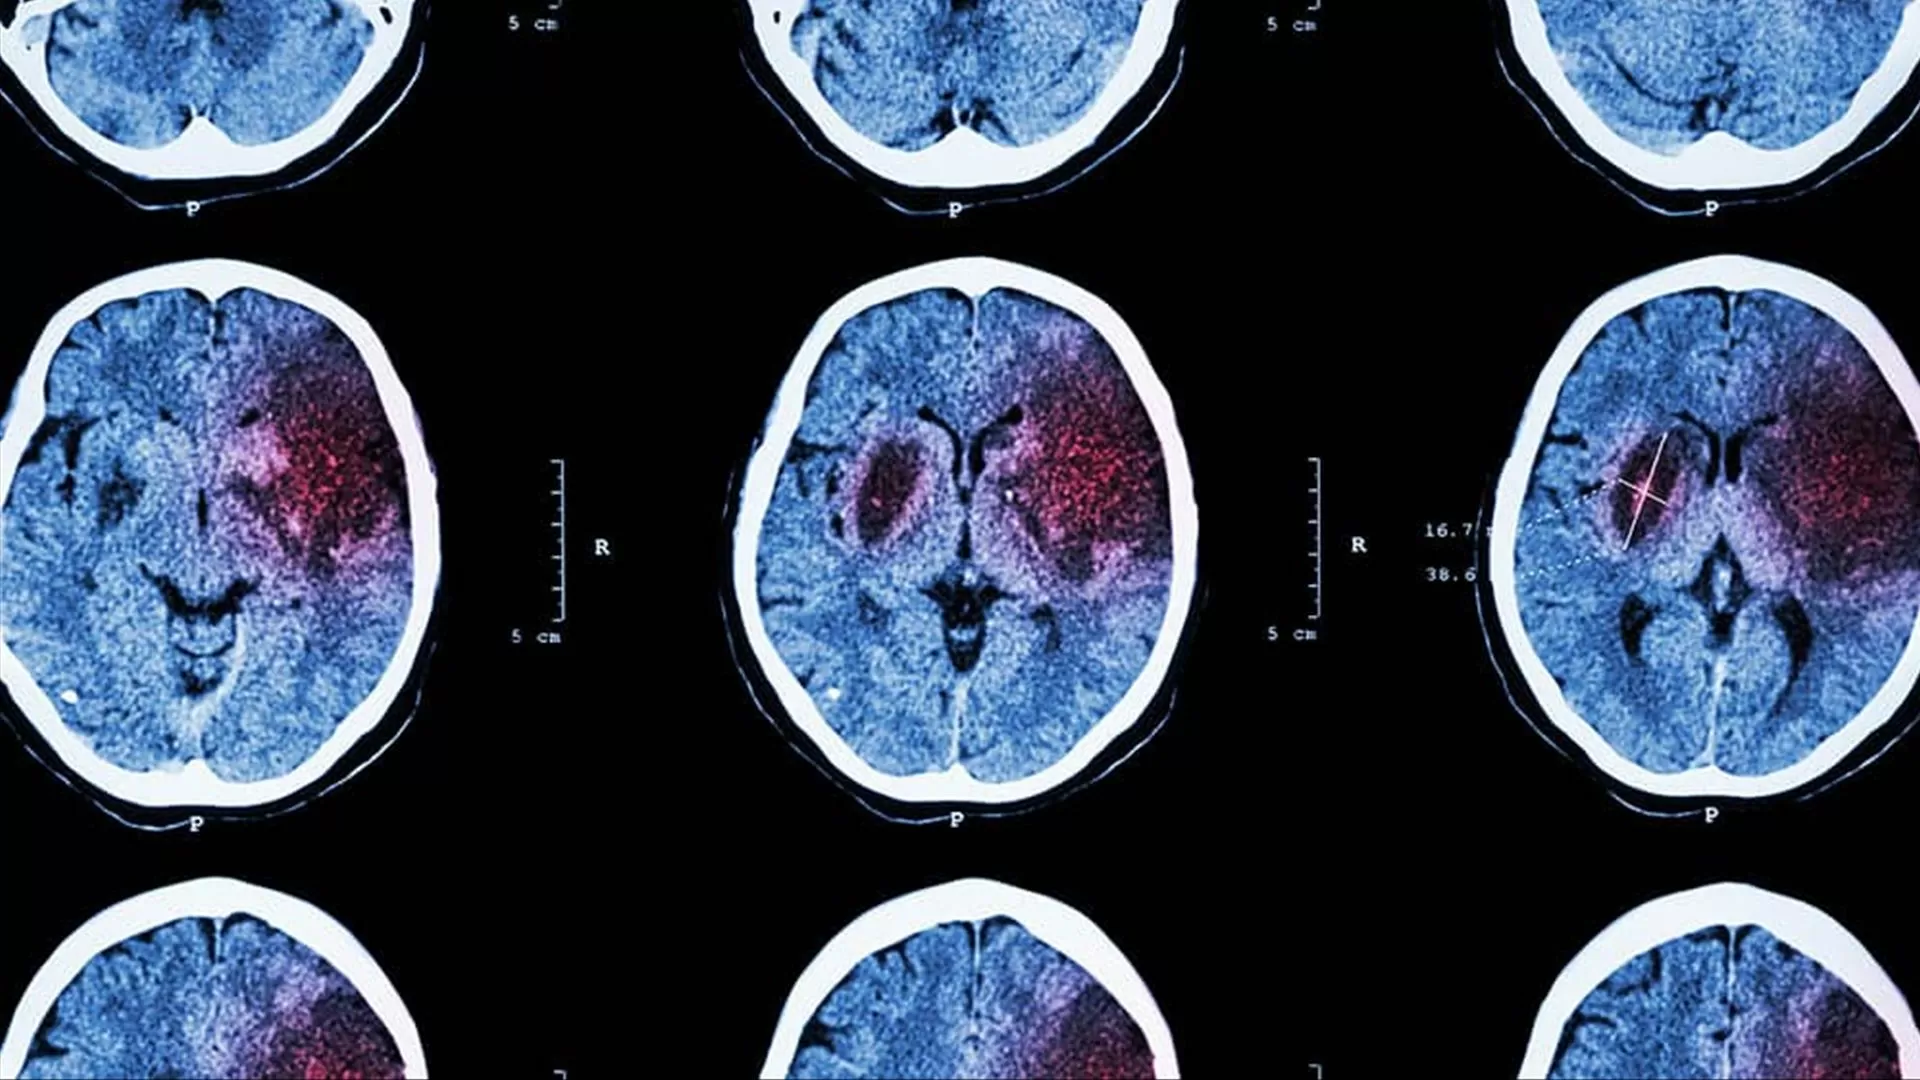

Os pesquisadores utilizaram técnicas de neuroimagem para monitorar a atividade cerebral de voluntários enquanto eles realizavam tarefas que envolviam tomada de decisão. Eles descobriram que, além do córtex pré-frontal, outras regiões do cérebro, como o córtex parietal e o córtex cingulado anterior, também estavam ativas durante o processo de tomada de decisão.